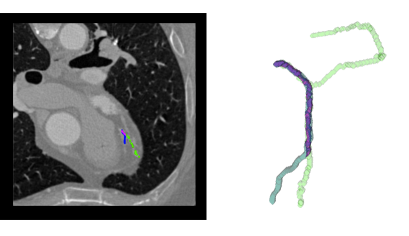

3.1.4 Coronary Data

In this experiment we tested our method for cardiac vessels segmentation. To evaluate our algorithm for such application, we used the coronary dataset provided for the MICCAI ”3D Segmentation in the Clinic: A Grand Challenge II” coronary. This database contains thirty-two cardiac CT datasets with reference data available for the four main coronary vessels. It is important to notice that the reference is composed by four single vessel segmentation, and therefore does not test the full potential of our method since they do not form a full vascular network. Nonetheless, it is a very interesting dataset and the available references can be used as guidance for visual assessment.

Figure 17 shows that the reference single vessel is among the branches segmented (in green) using our method, which segmented other two extra branches as well.

Considering the single vessel reference available for this dataset, an interesting effect is noticed. Since we use a single start point for segmenting the vascular network, a so-called ”blind effect” is observed. Even though the segmentation process segments the network and includes the reference single vessel, it also segments other branches, and therefore would be badly evaluated by the competition evaluation tool. If we restrict the algorithm to find a single path, then it is not possible to ensure a-priori which of the three detected branches would be chosen. Figure 18 depicts the effect.